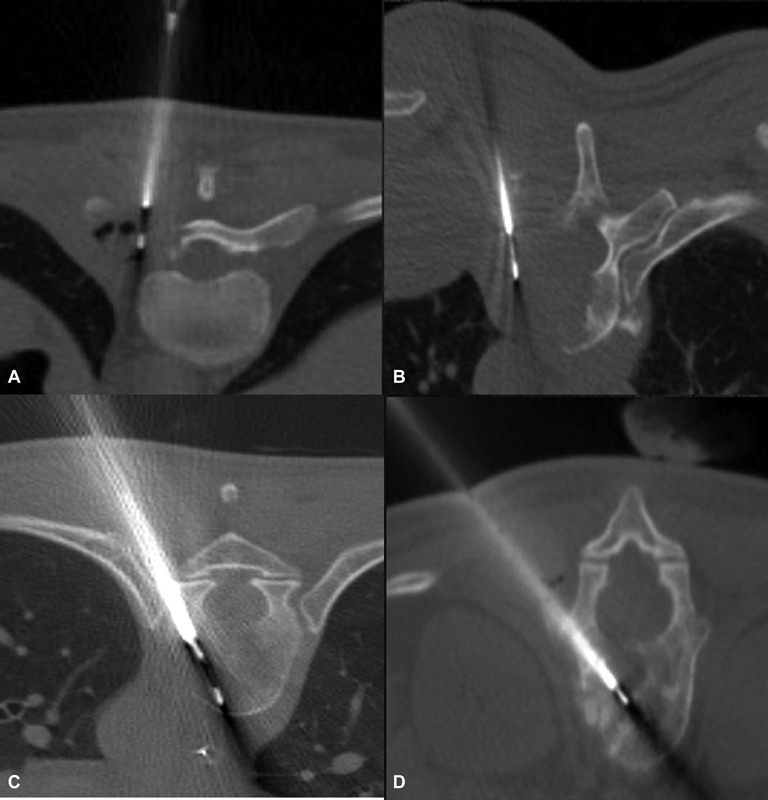

E)Spinal lesions-The biopsy of vertebral lesions depends on the location of the lesion within the vertebra and the level of vertebra. It can be transpedicular, parapedicular, transforaminal, and para laminar for lumbar and thoracic vertebrae. It can be an anterolateral, posterolateral, posterior, and anterior transoral approach under fluoroscopy or CT guidance for the cervical vertebra, depending on the location of the lesion[8] ([Fig. 3]).

| Figure 3:(A and B) Axial CT images demonstrate vertebral lesion biopsy by parapedicular technique. (C and D) Axial CT images demonstrate vertebral lesion biopsy by transpedicular technique.

| Figure 3:(A and B) Axial CT images demonstrate vertebral lesion biopsy by parapedicular technique. (C and D) Axial CT images demonstrate vertebral lesion biopsy by transpedicular technique.